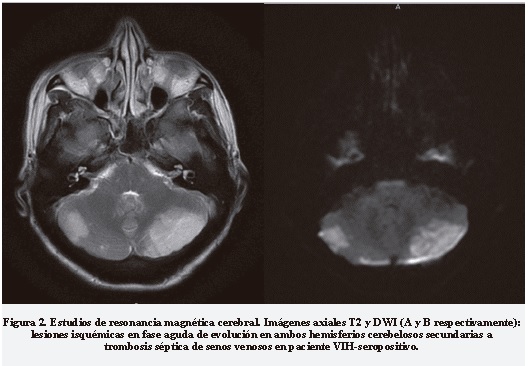

Mujer de 45 años de edad, con sida, quien ingresa por cefalea, fiebre, habla incoherente y crisis epiléptica generalizada. Al examen físico tuvo signos cerebelosos. La RMC y ARMC evidenciaron trombosis de senos venosos (sagital superior y transversos bilateral) asociada con infartos de la fosa posterior (Figura 2). El estudio de LCR hizo hallazgos típicos de CC con pleocitosis, hipoglucorraquia y antígeno capsular positivos. Fue tratada con anfotericina B más flucitosina durante dos semanas, luego presentó delirium hiperactivo, flebitis de miembro superior derecho, hipokalemia y prurito secundarios a aplicación de anfotericina B. Después de un mes de hospitalización se dio egresó con hemiparesia moderada.

Se realizaron RMC al 87,5% (n = 7) en dos pacientes (28,6%) que fueron reportadas como normales, en el resto (71,4%) se encontró alguna anormalidad: en dos pacientes (28,6%) se halló hidrocefalia, de los cuales uno tenía cambios radiológicos compatibles con ventriculitis; en otros dos se evidenciaron criptococomas (28,6%) y de dos más (28,6%) se documentó trombosis de senos venosos a través de ARMC (Tabla 3).

Cabe destacar que la trombosis venosa cerebral séptica por criptococo es poco frecuente, sin embargo en nuestro estudio se detectó esta presentación clínica en dos pacientes, un caso con compromiso de seno transverso y sigmoideo, y el otro con compromiso de seno sagital superior y transverso bilateral, quien desarrolló además infartos cerebrales de origen venoso, lo que contribuyó a un peor pronóstico con secuelas neurológicas importantes.